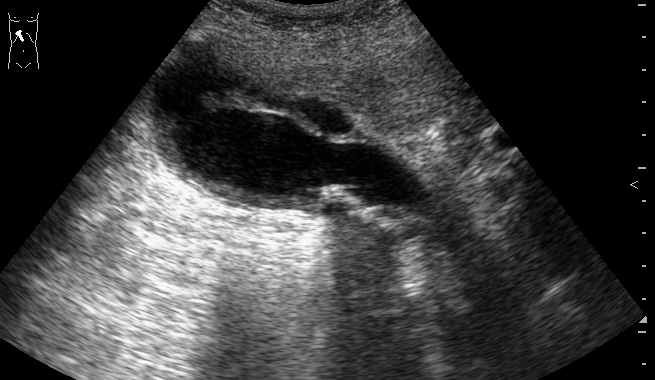

Пожилой мужчина, обратился в приемный покой БСМП с жалобами на периодические тупые боли в эпигастрии и правом подреберье. Год назад были сильные боли в правом подреберье, лечился самостоятельно дома.

слизистая в просвете желчного пузыря, что говорит о некрозе его стенки ... острый калькулезный холецистит, с перфорацией..

Острый калькулезный гангренозный холецистит.

Особенность этого случая в том, что создается впечатление о перфорации стенки пузыря в области дна и наличии скопления желчи в области ложа пузыря.

В действительности перфорации стенки пузыря не было.